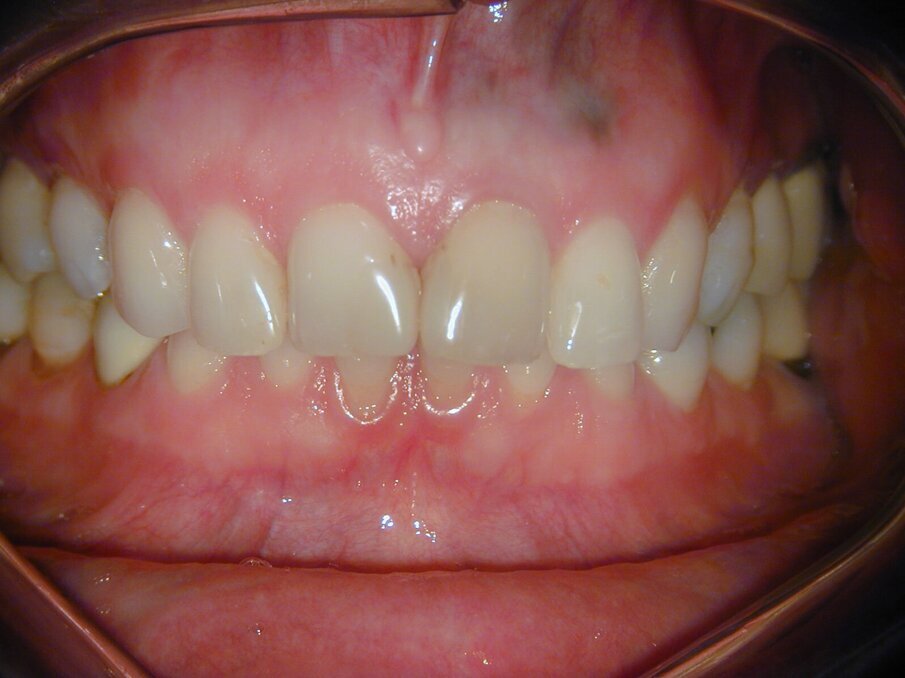

De laatste röntgenfoto en klinische foto’s laten een 37-jarige follow-up zien, waarbij op te merken valt dat ook de amalgaam vullingen 37 jaar geleden werden gelegd (afb. 8-11). De patiënt is volledig klachtenvrij en nog steeds tevreden met het tandheelkundige werk in haar mond.

Afb. 9-11: Klinische foto’s van de 37-jarige follow-up